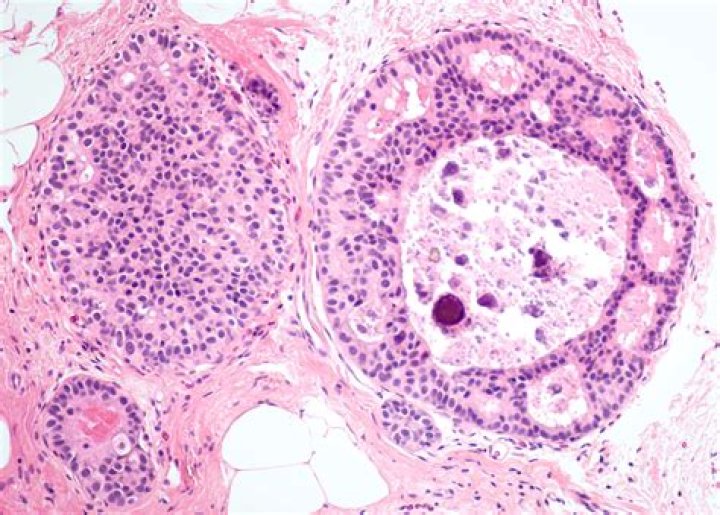

Lobular Carcinoma In Situ. Lobular Carcinoma in Situ (LCIS) is a malignancy of the secretory lobules of the breast that is contained within the basement membrane (Fig. 3). They are much rarer than DCIS however individuals with LCIS are at greater risk of developing an invasive breast malignancy.

What is LCIS classic type?

Classic LCIS is a monomorphic, dyshesive proliferation of non-polarized cells with round to oval shape, inconspicuous cytoplasm. The nuclei are located in the center of the cells, and are small, round to oval, with smooth nuclear membrane and inconspicuous nucleoli (Fig. 3). Cell borders are indistinct.